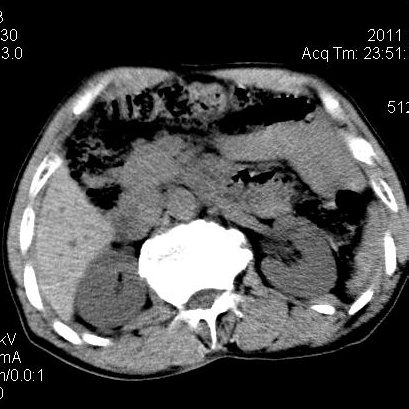

肝左叶发育异常

男性,55岁,骑摩托车摔倒后入院,自述右上腹疼痛

[backcolor=#FF0000]第一次诊断的时候也是这么肯定,可是床旁超声检查并没有发现明显异常,而且患者的一般症状都良好。还好临床只是保守治疗,没有立即手术,第二次复查的时候没有一点变化,又做了MRI检查,没有血肿,

这是一例肝左叶发育异常的,很个性吧~[/backcolor]